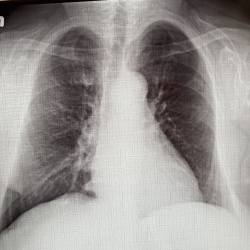

Пожалуйста посмотрите рентген лёгких

Расшифруйте пожалуйста снимок лёгких моей бабушки. Ей 72 года.

С учетом качества изображений - в пределах возрастных изменений (диффузный пневмосклероз, атреросклероз аорты,дегенеративные изменения позвоночника. Ничего более серьёзного не найдено.